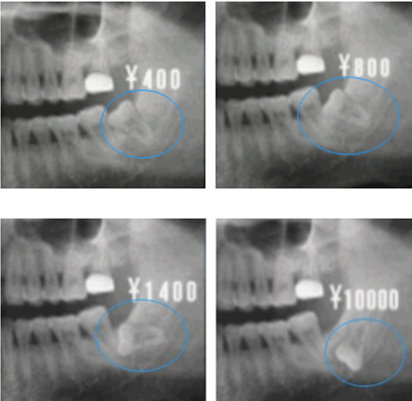

大部分的智齒都是這樣長歪的,而且長歪的程度不同,拔牙價(jia) 格也不同